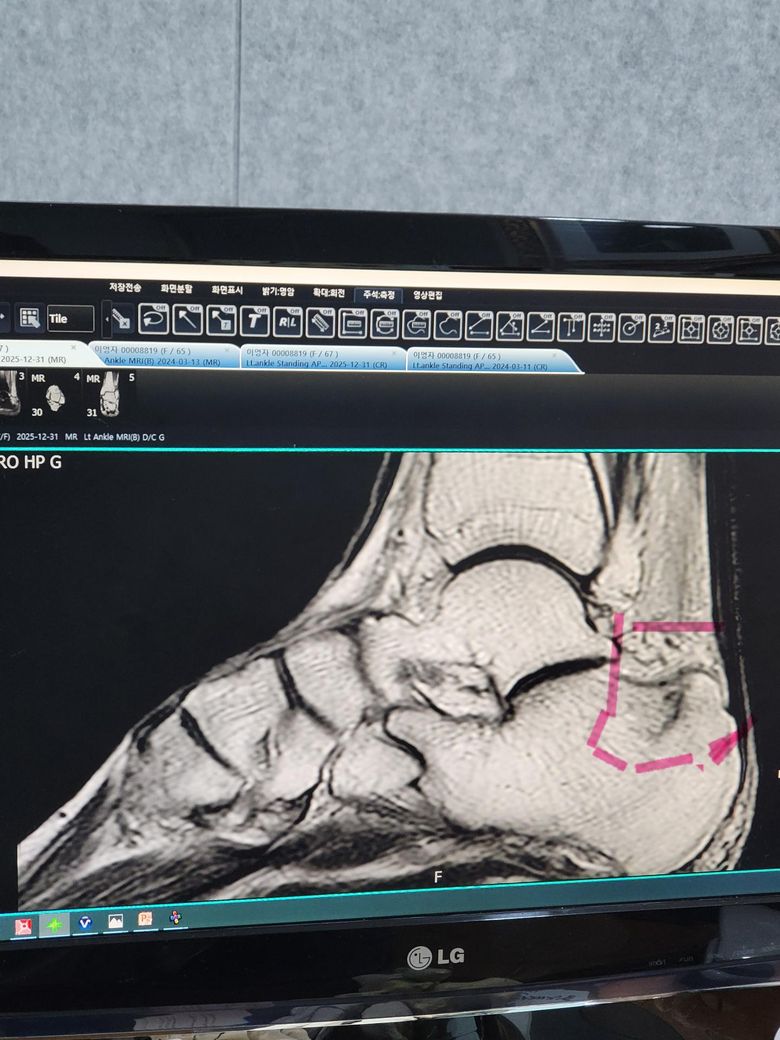

• 사진을 기준으로 보면 발뒤꿈치뼈(종골) 후방에 미세 골손상 또는 스트레스 손상 범위가 표시된 영상으로 보입니다. 이런 경우 좋아졌는지를 판단하는 기준과 기간은 비교적 명확합니다.

첫째, 증상 기준입니다. 체중을 실어 걸을 때 통증이 거의 없거나 일상 보행 시 통증이 재발하지 않으면 임상적으로는 호전 단계로 봅니다. 보통 3~4주부터 통증 감소가 뚜렷해지고, 6주 전후가 되면 통증 기준으로는 회복 여부를 판단할 수 있습니다.

둘째, 영상 기준입니다. MRI에서 보였던 골수 부종이나 미세 손상은 증상보다 늦게 사라집니다. 실제로는 통증이 거의 없어져도 MRI 소견은 2-3개월까지 남아 있는 경우가 흔합니다. 따라서 “완전히 나았는지”를 영상으로 확인하려면 최소 8주, 보수적으로는 10-12주 정도를 잡습니다.

셋째, 현재 상태 평가입니다. 약을 잘 드시고 재활·근력운동을 꾸준히 하고 계시다면 회복 경과는 좋은 편입니다. 다만 통증이 남아 있는 상태에서 운동 강도가 과하면 회복이 늦어질 수 있으므로, 통증이 기준입니다. 걷고 난 뒤 통증이 다음 날까지 남지 않는지가 중요한 지표입니다.

정리하면, 통증 기준으로는 6주 전후, MRI로 “정상화 여부”를 보려면 2~3개월 정도를 예상하시면 됩니다. 6주가 지나도 뒤꿈치 통증이 분명히 남아 있다면 운동 강도 조절과 함께 재평가가 필요합니다.